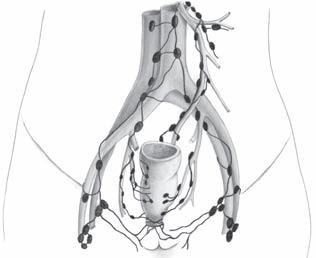

Lymfatický systém

Lymfatická síť rekta se dělí na dvě teritoria, jejichž rozdělení je dáno třetí Houstonovou chlopní (obr. 2.4). Toto dělení je podloženo embryologickým vývojem. Horní rektum (endodermální list) má cévní zásobení ze systému abdominálního, zatímco dolní rektum (ektodermální list) ze systému pelvi-parietálního.

1. Dolní lymfatický pedikl, ganglia ingvinální, sakrální a ilická. Primární kolektory pokračují lymfatickou sítí dvou dolních hemoroidálních pediklů do ingvinálních

paraaortální uzliny aorta

vasa iliaca int.

Obr. 2.4 Lymfatické šíření karcinomu rekta

vasa mesenterica inf.

vasa iliaca ext.

ganglií. Jde o drenáž oblasti laterálních sakrálních tepen zaujímající teritorium až po promontorium a o oblast arteria pudendalis interna, která sahá až po odstup vnitřní ilické tepny.

2. Střední lymfatický pedikl drénuje oblast střední rektální tepny až po ganglion hypogastricum. Tento pedikl je spojen s horním prostorem pelvi-rektálním a s oblastí arteria sacralis mediana, která sahá až po promontorium.

3. Horní lymfatický pedikl – abdominální – vzniká spojením všech mukózních lymfatických sítí dolního i horního rekta s uzlinovými spojkami intraparietálními (Gorotovy lymfatické uzliny) a s uzlinovými spojkami extraparietálními – pararektálními (Cuneovy lymfatické uzliny). V průběhu vasa rectalis superior nacházíme lymfatické uzliny Mondorovy, v oblasti odstupu arteriae sigmoideales jsou lokalizovány lymfatické uzliny Cuneovy. Vzdálené lymfatické kolektory jsou v oblasti odstupu arteria colica sinistra z arteria mesenterica inferior (podle Jamieson-Doobsona) nebo na počátku arteria mesenterica inferior (Moynihamovy lymfatické uzliny). Tyto lymfatické cesty končí v uzlinách paraaortálních, nebo sledují vena mesenterica inferior, a pak končí v uzlinách retropankreatických či paraportálních na soutoku žíly lienální, dolní a horní mezenterické v žílu vrátnicovou [5, 8, 16, 19, 23].

Horní třetina rekta má tedy hlavní lymfatickou drenáž probíhající podél arteria rectalis superior a arteria mesenterica inferior do paraaortálních lymfatických uzlin. Menší význam má pak lymfatická drenáž podél vena rectalis superior a pak podél vena mesenterica inferior směřující do paraportálních lymfatických uzlin. Pro dolní dvě třetiny rekta existují dva lymfatické systémy. I pro dolní třetiny rekta je převažující drenáž lymfatickým systémem podél vasa rectalis superior a vasa mesenterica inferior. Laterální lymfatická drenáž podél vasa rectalis media směřuje podél vasa iliaca

interna do lymfatických uzlin podél vasa iliaca communis. Četné studie využívající lymfoscintigrafii demonstrují komunikace mezi lymfatickými uzlinami podél vasa mesenterica inferior a vasa iliaca interna [14, 15, 18, 21]. Aborální třetina rekta nad linea dentata je drénována převážně cestou lymfatického systému podél vasa rectalis media a rectalis inferior do vnitřních ilických lymfatických uzlin. Šíření maligních buněk z této lokalizace může být nalezeno také v lymfatickém systému podél vasa rectalis superior a vasa mesenterica inferior. Aborálně od linea dentata směřuje lymfatická drenáž podél vasa rectalis inferior do povrchních ingvinálních uzlin. Lymfangiografie ukázaly u žen lymfatickou drenáž rekta směřující do lymfatických uzlin podél cévních svazků ženských reprodukčních orgánů [3, 21, 23]. Detailní anatomické studie se zaměřily na diseminaci maligního tumoru rekta lymfatickým systémem s cílem posoudit vliv radikální en bloc provedené pelvické lymfadenektomie na přežívání nemocných. Gabriel et al. [9] provedli detailní disekci a anatomické zmapování lymfatických uzlin u 100 nemocných s karcinomem rekta. Metastázy v lymfatických uzlinách byly nalezeny u 62 % nemocných. Šlo o postupné metastazování – progresi tumoru – do perirektálních uzlin, pak podél vasa rectalis superior a konečně do uzlin probíhajících podél vasa mesenterica inferior. Jen v jednom případě byly metastázy nalezeny v uzlinách proximální mezenterické ligatury, přestože nebyly nalezeny metastázy v uzlinách periferních etáží. Výskyt metastáz ve vzdálených lymfatických uzlinách bez postižení perifernějších lymfatických etáží je však v dalších studiích častější, Wood a Wilkie udávájí 12 % a Grinnell 17 % [14, 26]. Grinnellova studie také ukázala, že více než polovina lymfatických uzlin s metastázami karcinomu rekta byly lymfatické uzliny lokalizované do 3 cm od primárního tumoru. Z této studie je očividné, že široká resekce lymfatické tkáně musí být nutná k odstranění postižených či potencionálně postižitelných regionálních uzlin. Retrográdní diseminace či invaze tumoru aborálně stěnou rekta byly objeveny zcela ojediněle. Retrográdní metastazování lze patrně nalézt na podkladě embolie tumorózních buněk jako výsledek blokády primární lymfatické drenáže [4, 9, 10, 15, 25]. Šíření maligních nádorů rekta směrem aborálním ve stěně rekta sledovali Grinnell a Gilchrist [11, 15]. U 5 % vyšetřovaných preparátů nalezli šíření tumoru mukózní lymfatickou sítí pod resekční linii, která byla 2 cm aborálně od tumoru. Sauer a Bacon se zaměřili na možnost šíření maligního tumoru laterálně podél střední rektální tepny. Aplikovali in vivo Evansovu modř do submukózy dolního rekta a prokázali komunikaci lymfatického systému rekta podél vasa rectalis media s lymfatickým systémem dna pánevního, levátorů a reprodukčních orgánů [1].